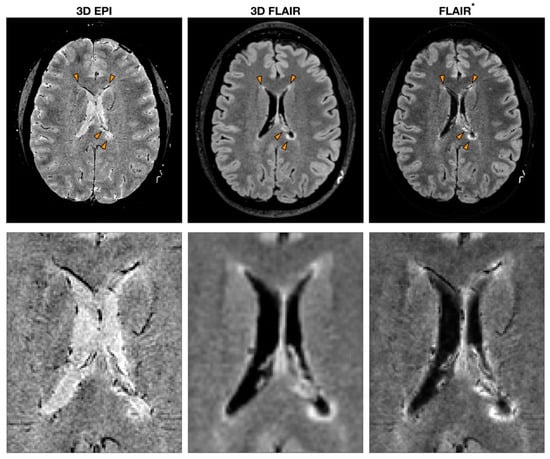

- Sati, P.; George, I.C.; Shea, C.D.; Gaitán, M.I.; Reich, D.S. FLAIR*: A combined MR contrast technique for visualizing white matter lesions and parenchymal veins. Radiology 2012, 265, 926–932. [Google Scholar] [CrossRef]

- Campion, T.; Smith, R.J.P.; Altmann, D.R.; Brito, G.C.; Turner, B.P.; Evanson, J.; George, I.C.; Sati, P.; Reich, D.S.; Miquel, M.E.; et al. FLAIR* to visualize veins in white matter lesions: A new tool for the diagnosis of multiple sclerosis? Eur. Radiol. 2017, 27, 4257–4263. [Google Scholar] [CrossRef]

- Gabr, R.E.; Pednekar, A.S.; Kamali, A.; Lincoln, J.A.; Nelson, F.M.; Wolinsky, J.S.; Narayana, P.A. Interleaved susceptibility-weighted and FLAIR MRI for imaging lesion-penetrating veins in multiple sclerosis. Magn. Reson. Med. 2018, 80, 1132–1137. [Google Scholar] [CrossRef]

- Gaitán, M.I.; Yañez, P.; Paday Formenti, M.E.; Calandri, I.; Figueiredo, E.; Sati, P.; Correale, J. SWAN-venule: An optimized mri technique to detect the central vein sign in ms plaques. AJNR Am. J. Neuroradiol. 2020, 41, 456–460. [Google Scholar] [CrossRef]

- George, I.C.; Sati, P.; Absinta, M.; Cortese, I.C.; Sweeney, E.M.; Shea, C.D.; Reich, D.S. Clinical 3-tesla FLAIR* MRI improves diagnostic accuracy in multiple sclerosis. Mult. Scler. Houndmills Basingstoke Engl. 2016, 22, 1578–1586. [Google Scholar] [CrossRef] [PubMed]